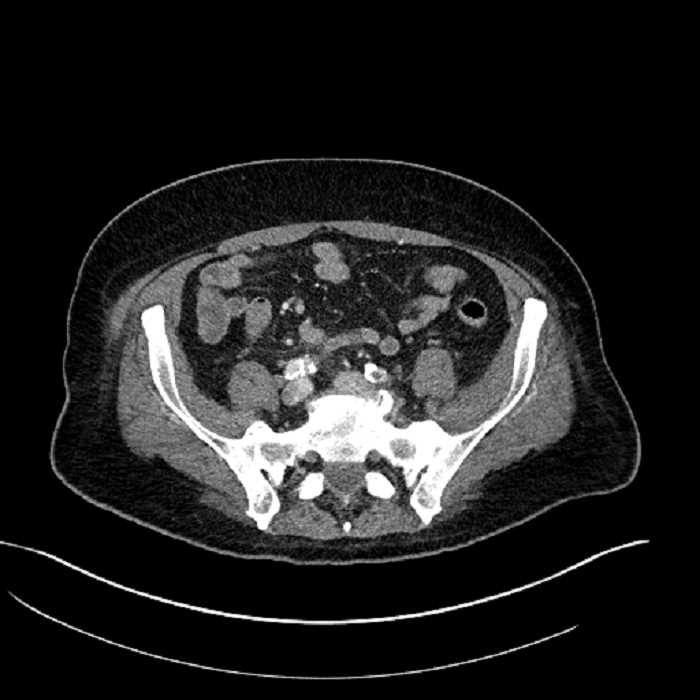

Age: 63

Sex: Male

Indication: Abdominal pain

• Large fluid density structure in hepatic segments 7 and 8 measuring 10 x 7 x 7 cm with internal septation and circumferential ill-defined low density compatible with edema

• Peripherally enhancing subcapsular collections along the anterior margin of the left hepatic lobe measuring 3 x 1 cm and 2 x 1 cm

• Clearly marginated fluid density structure in segment 7 and several other scattered tiny hypodensities, which likely represent cysts

• Mild mural thickening of a segment of the sigmoid colon with adjacent fat stranding and a 1.5 cm fluid and gas collection along the tip of an inflamed diverticulum

• Loss of the normal fat plane between this collection and adjacent loops of small bowel, which demonstrate mural thickening

Acute sigmoid diverticulitis complicated by a small contained perforation and a large abscess in the right hepatic lobe. Additional small subcapsular abscesses along the anterior margin of the left hepatic lobe.

Additionally, loss of the normal fat plane between the peridiverticular collection and adjacent thickened loops of small bowel raises the potential for an enterocolonic fistula.

• The classic CT imaging appearance is a double target sign with internal low density surrounded by an internal enhancing rim (capsule) and a low density external rim (edema)

Hepatic abscess showing the double target sign with low density internally surrounded by a thin inner enhancing rim (red arrow) and ill-defined outer low density rim (yellow arrow). Blue arrow indicates an internal septation. Red arrows: additional smaller subcapsular abscesses. Red arrow: focal contained perforation associated with diverticulitis.